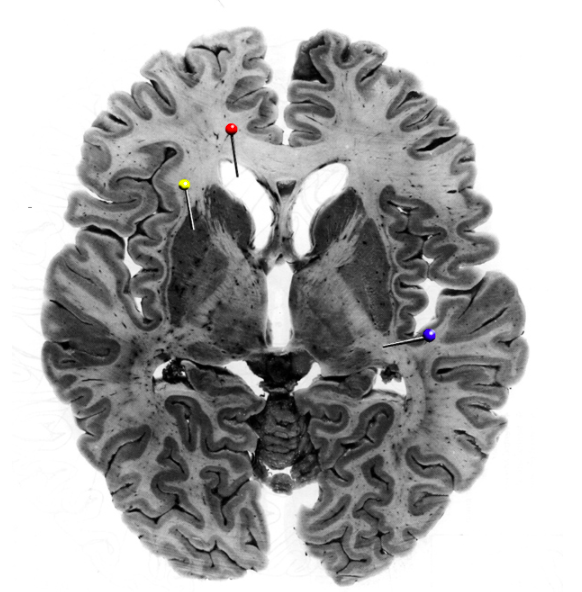

In this horizontal brain slice, the yellow pin is in

the thalamus

the caudate nucleus

the putamen

the globus pallidus

putamen